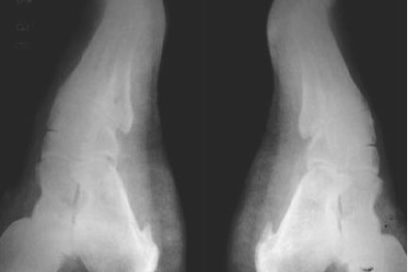

¿Y qué es el espolón calcáneo?

Es un crecimiento óseo sobre el hueso del talón, en especial en la parte inferior delantera del referido hueso, que se une con la fascia plantar: banda larga de tejido conectivo que se extiende desde el talón hasta la base de los dedos del pie, y cuando se estira excesivamente puede provocar ese crecimiento óseo o espolón.

La fascia plantar sostiene el arco longitudinal de la planta del pie y sirve para amortiguar los impactos durante las actividades de la vida diaria. El dolor se produce como consecuencia del esfuerzo y la inflamación de esta al tirar del hueso y comprimir una bolsa que rodea el espolón porque este demora mucho tiempo en formarse y puede pasar inadvertido por muchos años. Pero los microtraumas repetidos debido a deformidades como pies planos, exceso de arco, sobrepeso corporal, actividades físicas con calzados inadecuados y otras agresiones a los pies, son los desencadenantes de estos dolores. El espolón es un fenómeno secundario y no el origen del dolor.